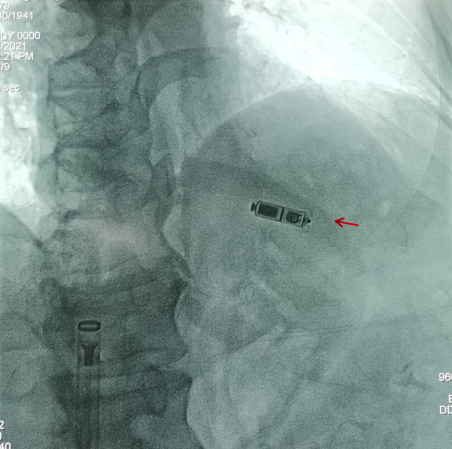

患者田某某,80 岁,男性,动态心电图示短暂全心停搏(5.2 秒),不纯性心房扑动,诊断:心律失常—短暂全心停搏、心房扑动,有永久心脏起搏器植入术适应症,但该患者事发 2 周前突发急性脑梗死,当时不宜停用抗血小板药物,传统起搏器植入常规需停抗血小板药物 5-7 天,且患者高龄,存在一定程度的认知功能障碍,上肢随意活动较大,对传统起搏器难以耐受,此外还合并糖尿病,存在切口愈合延迟及囊袋感染风险高等,有植入无导线心脏起搏器适应症。

经科室集体讨论后认为该患者适合无导线心脏起搏器植入,无手术禁忌症。在与患者及家属详细沟通并同意后,在潘朝锌主任医师带领下,黄明剑副主任医师完成经导管无导线心脏起搏器植入术。

术后患者心率恢复至正常范围,心动过缓相关症状明显改善,术后第一天即下床活动,无头晕、胸闷、乏力等不适症状,术后第三天康复出院。

而无导线起搏器比传统起搏器体积小 95% 以上,兼容 3.0T 核磁共振全身扫描,自动阈值管理,使用寿命长达 12 年,并且无传统起搏器电极脱位、囊袋破溃、感染等手术并发症。